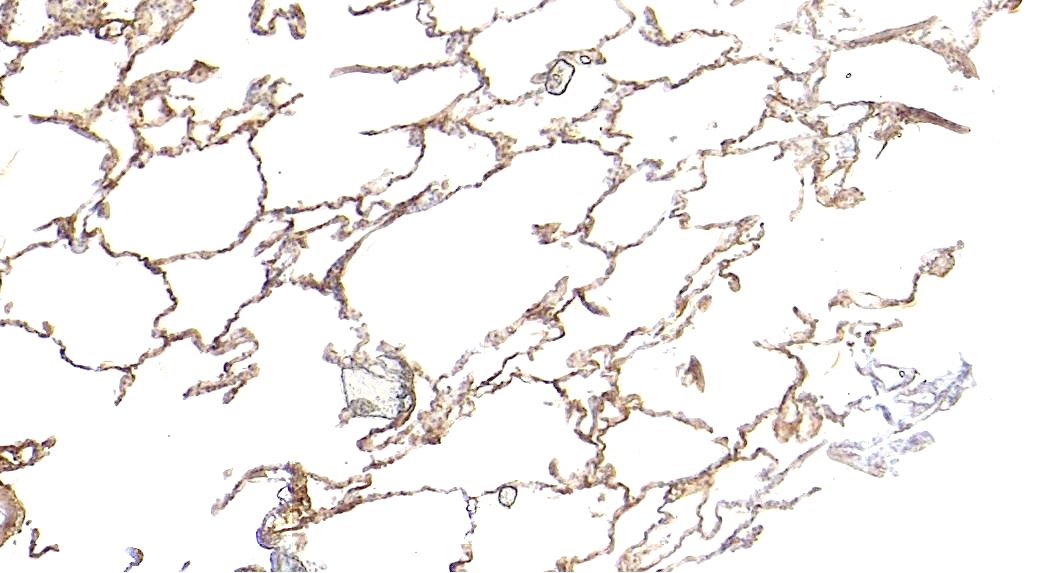

IHC Results Paraffin embedded Human Lung. Recommended concentration: 5-6µg/ml. | |